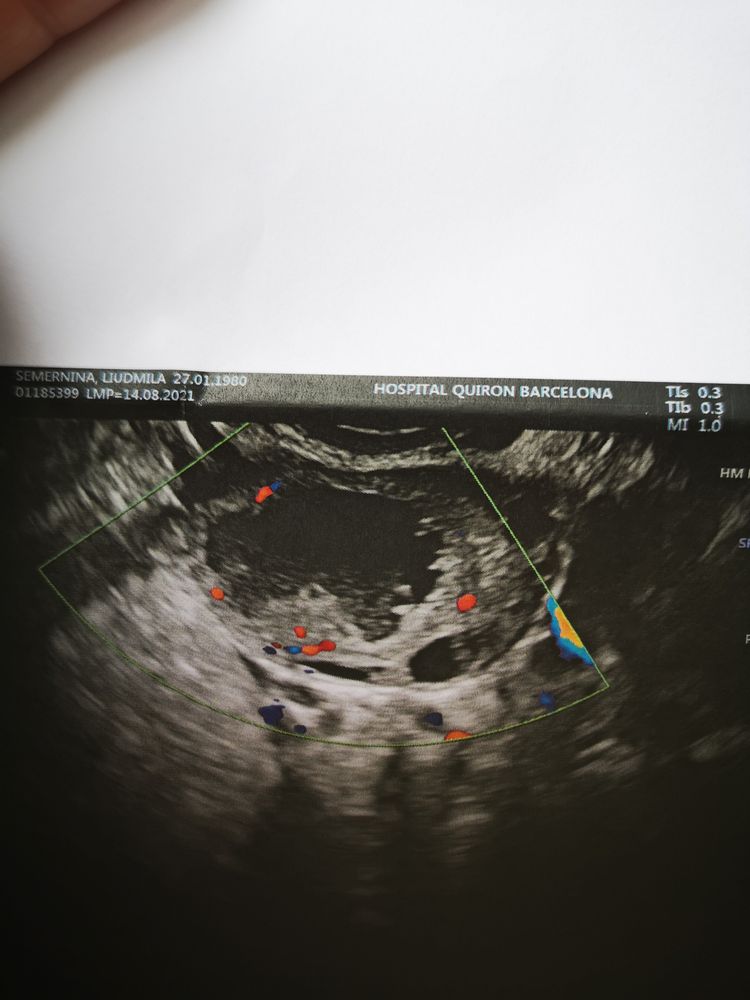

Скоро два раза мама!!!))), а есть фото? У меня сейчас тоже по вопросом жт или фоликул лютинизировался. Узист под вопросом поставила.

Женя Ветлова, у меня больше на жт похоже чем на дф, у вас на дф,размер 26 мм и тоже бт второй фазы.

Мила, да, очень похоже!

Мила, нет, фото нет. На экране только видела. Очень похоже на ЖТ, зернистое такое, серое. А тут у девушки больше на обычный фолликул похоже.

Скоро два раза мама!!!))), а на мое похоже? Фото выше? Вот думаю что это?))